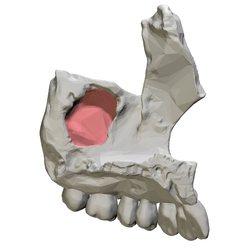

Left maxilla, medial view. Maxillary sinus shown in red.